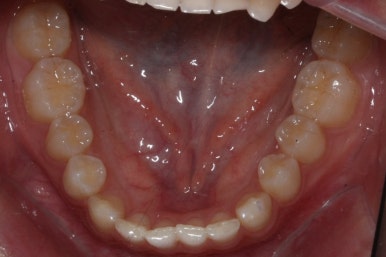

위 사진들은 부산매복치아교정 키다리아저씨치과에 처음 내원하셨을 때의 모습입니다.

화살표 표시한 부분이 바로 영구치 송곳니가 있어야 할 자리인데, 매복이 되어있고 대신 유치가 여전히 남아있는 모습입니다.

이번 환자분의 경우는 아랫니는 약간 삐뚤함이 있지만 굳이 교정치료를 원하지 않으셨기 때문에 윗니들만 부분교정으로 해결하기로 했습니다.

아래치아는 여전히, 당연히 장치가 붙지 않은 채로 그대로 둡니다.